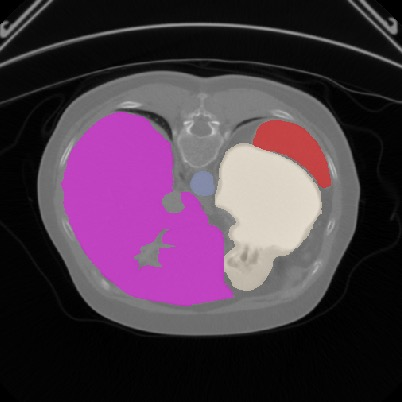

Transformers, the default model of choices in natural language processing, have drawn scant attention from the medical imaging community. Given the ability to exploit long-term dependencies, transformers are promising to help atypical convolutional neural networks (convnets) to overcome its inherent shortcomings of spatial inductive bias. However, most of recently proposed transformer-based segmentation approaches simply treated transformers as assisted modules to help encode global context into convolutional representations without investigating how to optimally combine self-attention (i.e., the core of transformers) with convolution. To address this issue, in this paper, we introduce nnFormer (i.e., Not-aNother transFormer), a powerful segmentation model with an interleaved architecture based on empirical combination of self-attention and convolution. In practice, nnFormer learns volumetric representations from 3D local volumes. Compared to the naive voxel-level self-attention implementation, such volume-based operations help to reduce the computational complexity by approximate 98% and 99.5% on Synapse and ACDC datasets, respectively. In comparison to prior-art network configurations, nnFormer achieves tremendous improvements over previous transformer-based methods on two commonly used datasets Synapse and ACDC. For instance, nnFormer outperforms Swin-UNet by over 7 percents on Synapse. Even when compared to nnUNet, currently the best performing fully-convolutional medical segmentation network, nnFormer still provides slightly better performance on Synapse and ACDC.